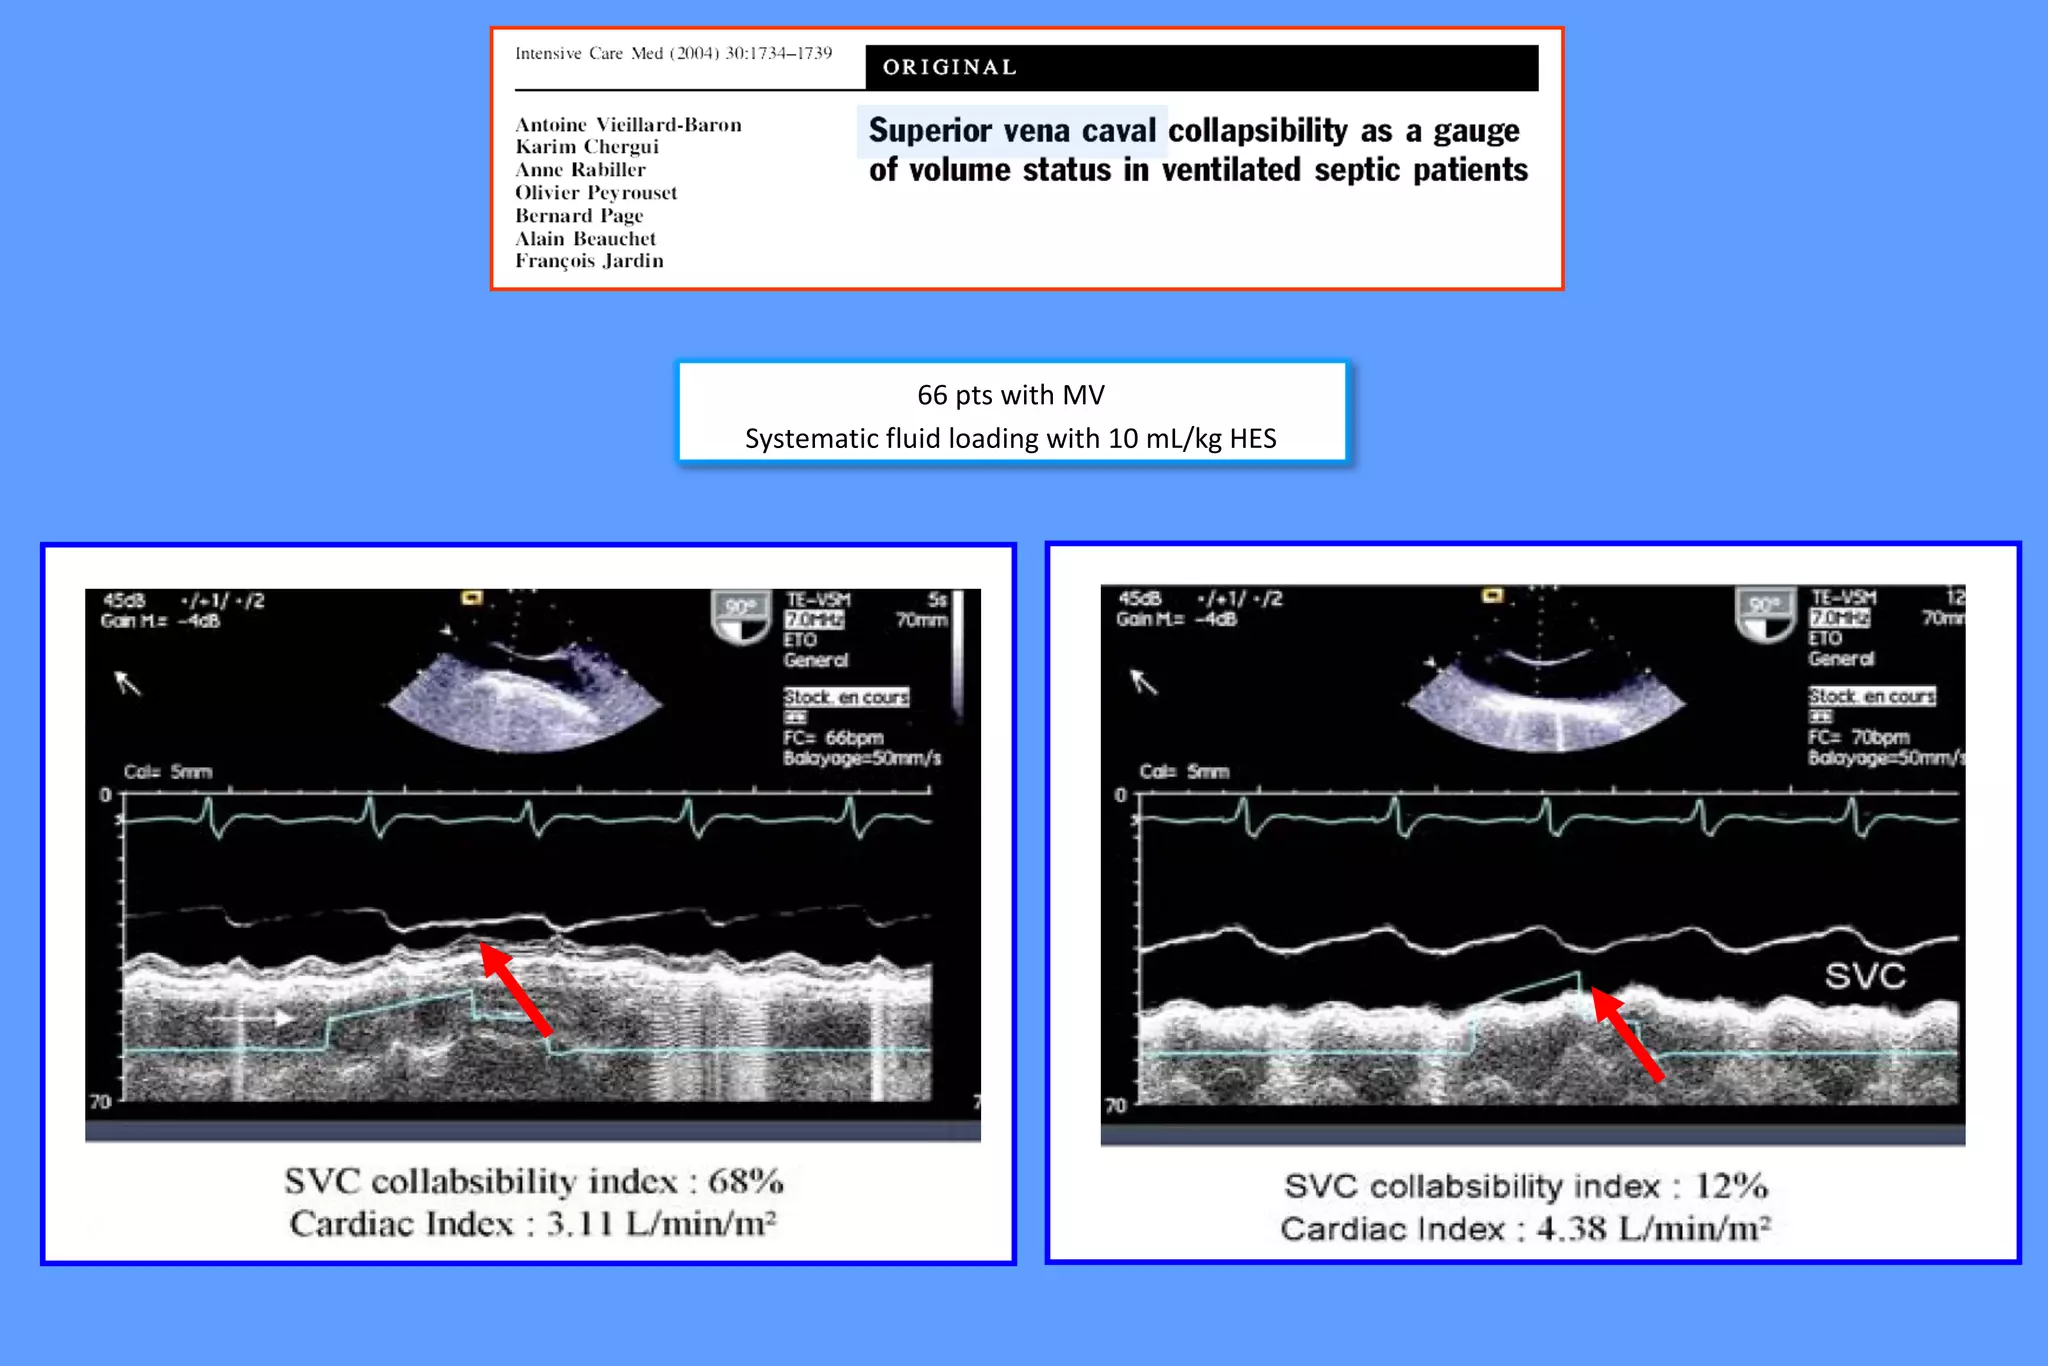

66 pts with MV

Systematic fluid loading with 10 mL/kg HES

PPV

SVC collapsibility

(AUC: 0.94)

(AUC: 0.99)

12%

36 %

PPV and SVC collapsibility

perform equally

for predicting fluid responsiveness

Transesophageal

approach

is required

66 pts withMV Systematic fluid loading with 10 mL/kg HES

0 20 4060 80 100 0 20 40 60 80 100 Specificity(%) 100 - Specificity (%) PPV SVC collapsibility (AUC: 0.94) (AUC: 0.99) 12% 36 % PPV and SVC collapsibility perform equally for predicting fluid responsiveness Transesophageal approach is required